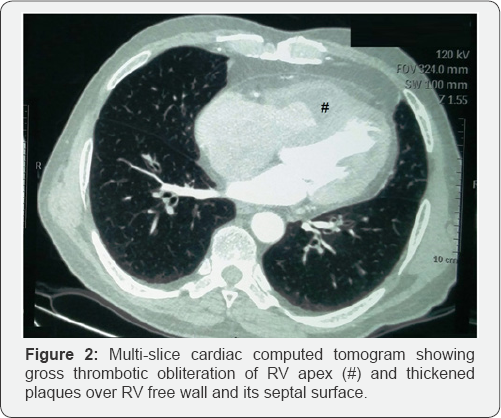

Hematological work-up revealed marked eosinophilic leucocytosis, with total leucocyte count of 11,400/cumm, 43% eosinophils, and absolute eosinophil count of 4902/cumm. Chest radiograph was normal with no pulmonary infiltrates. Electrocardiogram was suggestive of sinus tachycardia with incomplete right bundle branch block. Transthoracic echocardiogram revealed right ventricular (RV) dysfunction with obliteration of RV apex possibly with large thrombus (3x3cm) and mild tricuspid regurgitation with normal pulmonary artery pressure (Figure 1A). Left ventricle showed normal chamber dimensions with normal left ventricular systolic function and grade II diastolic dysfunction. Cardiac Computed tomography (CT) showed similar RV apical obliteration with mild RV dilation (Figure 1B). CT pulmonary angiogram was normal. Full array of differential diagnosis for etiology of eosinophila was investigated. Stool examination for parasite was negative. Polymerase chain reaction (PCR) of FIP1L1-PDGFRA gene rearrangement (For Chronic eosinophilic leukemia) was negative. Patient was not from endemic areas for filarial infection but surprisingly, IgG and IgM antibody assay for filaria was strongly positive. On the basis of investigations, a diagnosis of endomyocardial fibrosis (stage 2), secondary to hypereosinophilia related to filarial infection was made. Patient was started on diethylcarbamazine (100mg thrice a day for 14 days) and oral vitamin K antagonists for anticoagulation (INR range 2-3). He showed dramatic response to treatment, and his symptoms improved rapidly. At follow-up after 2 months, patient was asymptomatic; leucocyte count (10500/cumm), eosinophil differential count (2%), and absolute eosinophil count (208/cumm), were normalized; and apical RV thrombus and tricuspid regurgitation were completely resolved (Figure 2). Anticoagulation was stopped, and normal functional state and echocardiogram was found at repeat visit after 6 months.